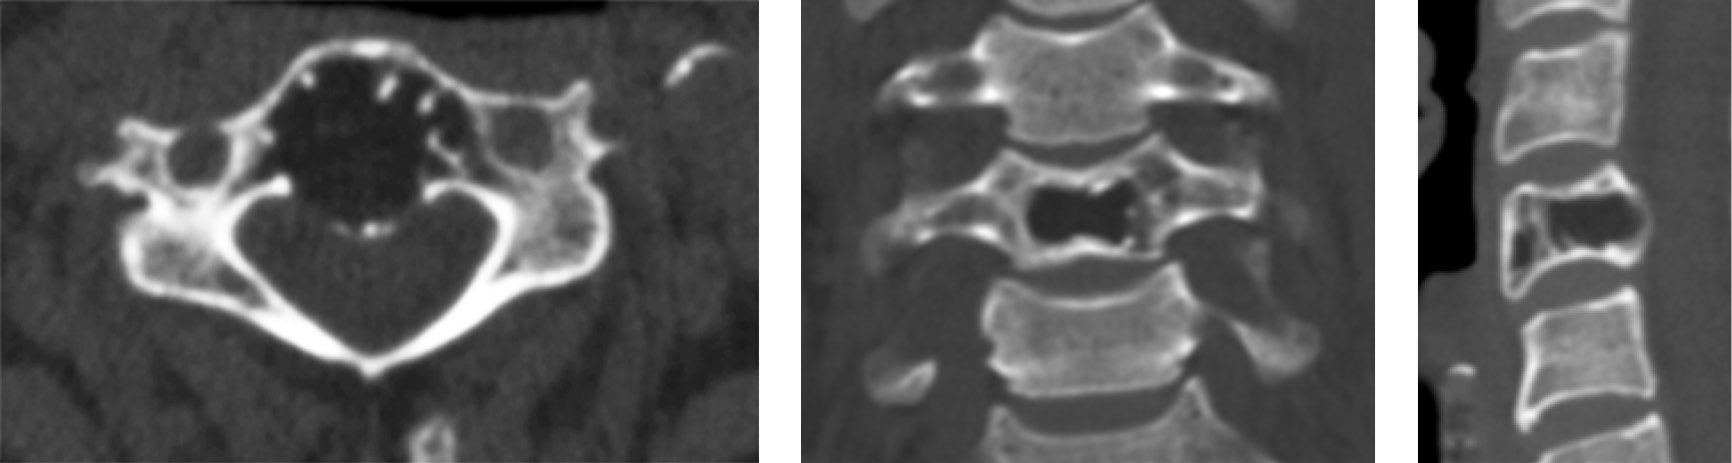

Open PV of the body of the vertebra Th1 was performed for the patient. After the surgery, the pain syndrome regressed. On postoperative CT images, the cavity was densely filled with polymethyl methacrylate (Fig. 4).

Fig. 4. CT scans of the vertebra Th1 of patient V. after the surgery

The efficiency of PV was evaluated as per the clinical data of complete regression of pain syndrome (up to 0 points as per the VAS in both patients). After the surgery, both patients underwent a check-up CT examination. On CT images, the completeness of filling the cavity with hemangiomas with bone cement was visualized, from 86% to 94% of filling. The duration of hospital stay was 2–4 days. Subsequent CT control was performed after 6 months, and the absence of relapsing growth of hemangiomas was confirmed.